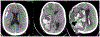

Results: Sixty-eight children met Duke criteria for infective endocarditis (43 definite and 25 possible). Twenty-three (34%) had identified neurologic complications, including intracranial haemorrhage (25%, 17/68) and ischaemic stroke (25%, 17/68). Neurologic symptoms began a median of 4.5 days after infective endocarditis symptom onset (interquartile range 1, 25 days), though five children were asymptomatic and diagnosed on screening neuroimaging only. Overall, only 56% (38/68) underwent neuroimaging during acute hospitalisation, so additional asymptomatic neurologic complications may have been missed. Children with identified neurologic complications compared to those without were older (48 versus 22% ≥ 13 years old, p = 0.031), more often had definite rather than possible infective endocarditis (96 versus 47%, p < 0.001), mobile vegetations >10mm (30 versus 11%, p = 0.048), and vegetations with the potential for systemic embolisation (65 versus 29%, p = 0.004). Six children died (9%), all of whom had neurologic complications.

Conclusions: Neurologic complications of infective endocarditis were common (34%) and associated with mortality. The true frequency of neurologic complications was likely higher because asymptomatic cases may have been missed without screening neuroimaging. Moving forward, we advocate that all children with infective endocarditis have neurologic consultation, examination, and screening neuroimaging. Additional prospective studies are needed to determine whether early identification of neurologic abnormalities may direct management and ultimately reduce neurologic morbidity and overall mortality.

Keywords: CHD; Infective endocarditis; infectious intracranial aneurysm; intracranial haemorrhage; neuroimaging; stroke.